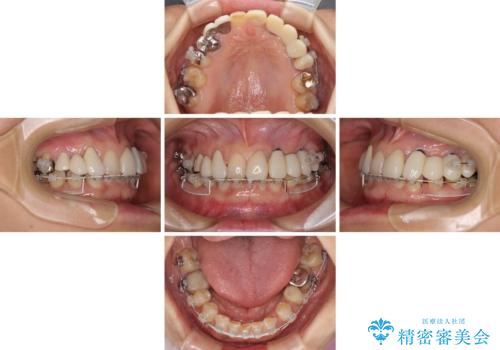

- 割れていると言われて放置してしまった歯や、前歯のデコボコなどが気になるとのことで来院された患者様です。

左上の歯は割れてしまっており、抜歯のうえインプラント治療が必要であり、他にも抜歯の必要な歯がある状態でした。

上顎はほぼ全ての歯をセラミッククラウンにて補綴治療を行う必要があるため、気になるデコボコや深い咬み合わせを改善するために下顎と上顎の臼歯部の矯正治療を行うこととしました。

並行して左下にはインプラントを埋入し、矯正治療を終えると同時に補綴治療を行うこととしました。

過蓋咬合(下顎前歯が隠れてしまうほどの深い咬み合わせ)のため、スムーズに歯が動かず矯正治療に時間がかかりましたが、無事に仕上げることができました。